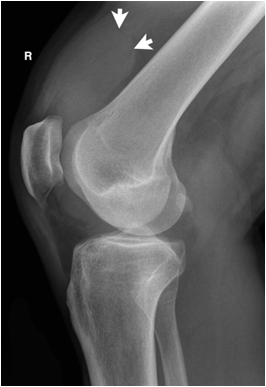

17.3.1 Soft tissue

In viewing the trauma film, soft tissue swelling, or foreign bodies have to be assessed. If foreign bodies are more dense than soft tissue (more radiopaque) they will be easily recognized (e.g. metal fragments or gravel). If they are less dense (e.g. gas) they will be seen only with close observation. Most exposures will require either a bright light or appropriate windowing on digital images to evaluate the soft tissues properly. If foreign bodies are not seen, they cannot be excluded as many types of glass, wood splinters or plastic have approximately soft tissue density.

Soft tissue swelling may be discerned not only by the apparent increase in the soft tissue but also by the interruption of normal fat planes. If subcutaneous fat or fat between muscle planes is infiltrated by edema (water density), the fat plane will no longer be visible since it loses its sharp contrast with water density structures like tendons or muscle.

Fig. 6. Patient with knee trauma. Plain films reveal significant suprapatellar joint effusion (white arrows). A fracture is not seen. MR imaging reveals a torn anterior cruciate ligament (white arrow head).